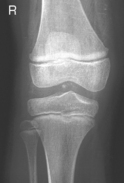

• Supine, or seated on table, with leg extended and centered to CR and midline of table or IR

• Rotate leg slightly inward as needed to place knee and leg into a true AP. Center IR to CR.